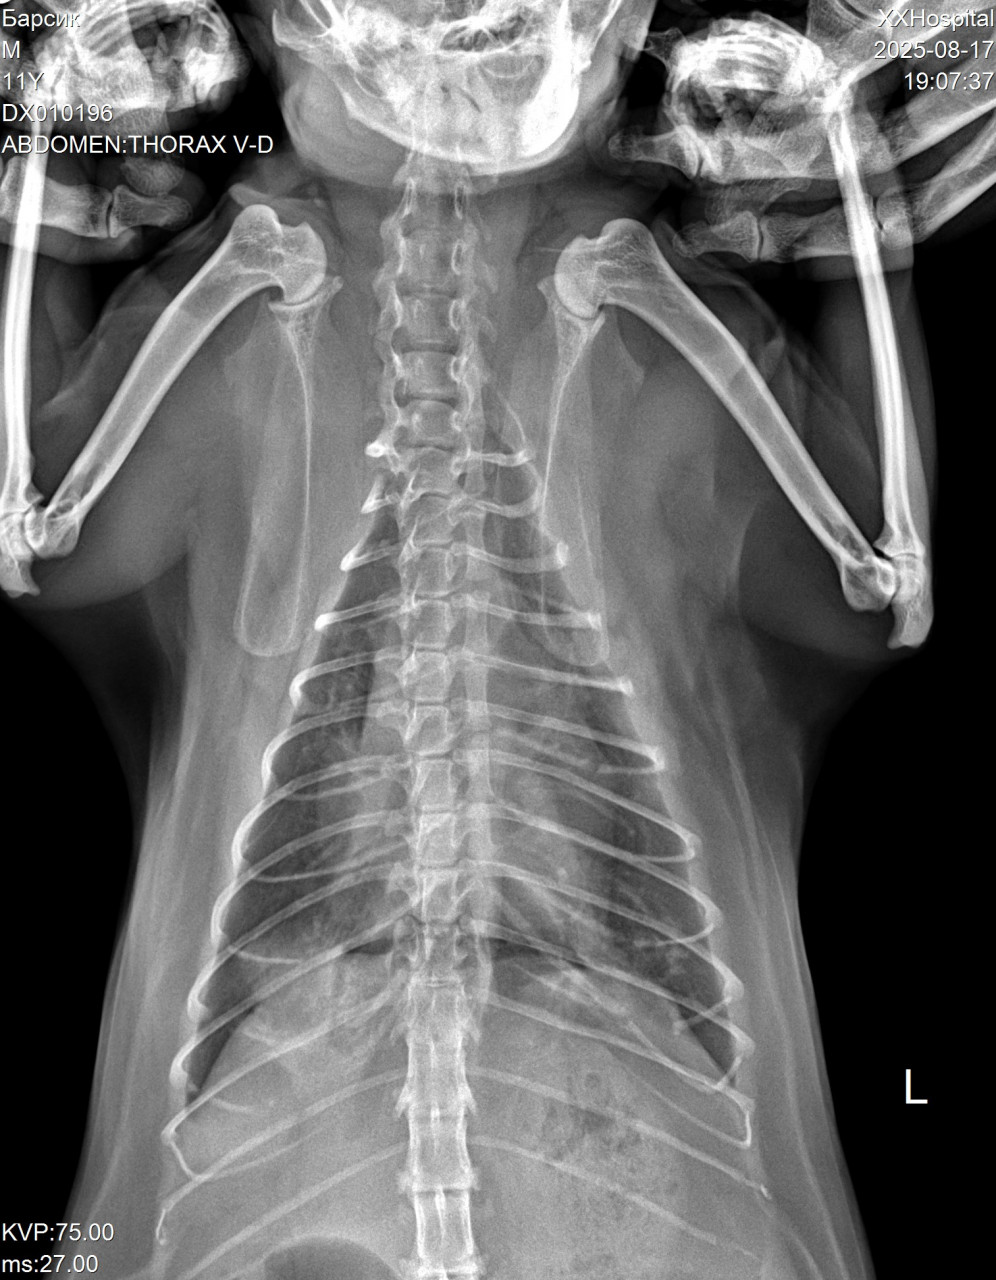

Кот стал хрипло мяукать. Ветеринар сказала сделать рентген грудной клетки. По снимкам сказала, что скорей всего новообразования, но не точно. Коту 12 лет.Также назначила кислород, и уколы ронколейкин, чтобы через неделю сделать повторно рентген. Велика ли вероятность, что это рак по снимкам?

Здравствуйте. По предоставленным рентген-снимкам грудной клетки у вашего кота действительно заметны изменения в области лёгких, которые могут соответствовать новообразованиям. Однако рентген не даёт 100% подтверждения диагноза «рак». Подобная картина может встречаться также при хронических воспалительных процессах (бронхит, пневмония), абсцессах или гранулёмах. Вероятность онкологии в 12-летнем возрасте повышена, особенно если изменения выглядят очаговыми или узловыми, но окончательно судить можно только после дополнительных исследований:

Здравствуйте. По рентген-снимкам у вашего кота действительно видны затемнения в грудной клетке, которые могут указывать на наличие новообразований. В то же время такие изменения иногда связаны с воспалительными процессами или скоплением жидкости поэтому только по рентгену окончательно сказать «рак» нельзя. В подобных случаях ветеринары ориентируются не только на снимки, но и на клинические проявления т.е на одышку, хриплое дыхание, кашель, общее состояние животного. Чтобы подтвердить или исключить опухоль, обычно рекомендуют дополнительные методы это повторный рентген, УЗИ грудной клетки, а при возможности и биопсию.